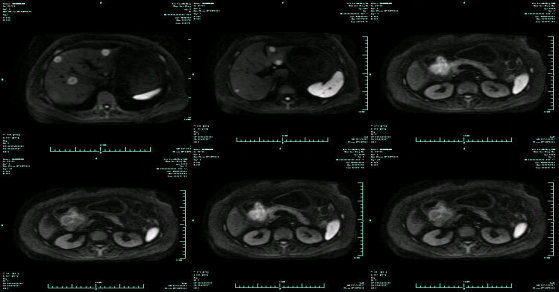

• 第三次FOLFOX+T方案后 B超提示肝转移灶消失

• 9 次FOLFOX+T+放疗

疗效评估:cPR

TOGA研究是第一个使用HER2抑制剂曲妥珠单抗治疗不能手术的局部晚期、复发或转移的HER2阳性胃癌患者的Ⅲ期临床研究。TOGA研究结果显示,IHC2+/FISH阳性或者IHC3+的患者与对照组相比,OS分别为16.0个月和11.8个月(HR为0.65)。曲妥珠单抗联合化疗显著提高了HER2阳性晚期转移性胃癌的治疗缓解率和总体生存率。2012年8月,曲妥珠单抗治疗HER2阳性转移性胃癌适应症在我国获批。对该患者进行病理切片会诊,幸运的是其HER2检测为阳性。随即进行靶向联合化疗治疗,三个周期后,肝转移灶消失,曲妥珠单抗治疗效果显著。九个周期的靶向治疗联合放化疗后,疗效评估cPR,随即行手术治疗。